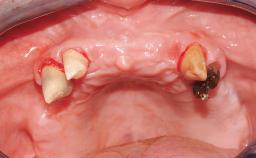

A healthy 31-year-old female patient presented with a failing maxillary left lateral incisor crown. The crown regularly loosened, and the remaining tooth was neither restorable nor rational to treat. The patient had a high smile line, a medium soft tissue biotype with a compromised mesial papilla (shorter than the contralateral one), and a horizontal scar in the buccal soft tissue as a result of past periapical surgery.

| Timing of placement | Immediate Placement (extraction sockets) (Type I) |

| Socket walls | Intact |

| Thickness of buccal wall | less than 2 mm |